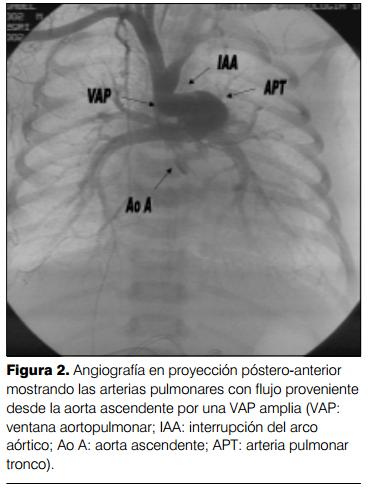

Cateterismo cardíaco (aortografía retrógrada) por vía arteria humeral derecha: a) interrupción del arco aórtico tipo A; b) ventana aortopulmonar tipo I, con importante cortocircuito de izquierda- derecha. Ductus arterioso permeable de pequeño calibre. Hipertensión arterial pulmonar a nivel sistémico con gradiente arteria pulmonar-ductus-aorta descendente de 30 mmHg. Dilatación de arteria pulmonar y cavidades izquierdas. FEVI normal (figuras 1, 2 y 3).